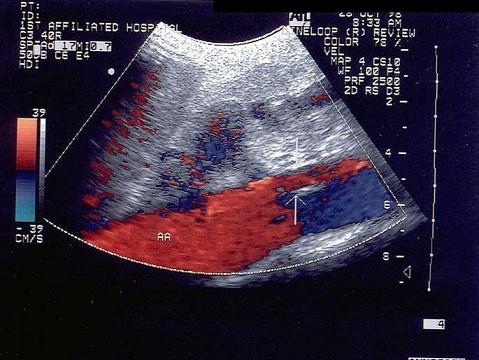

患者有高血压病史,最可能的诊断是?(?)A.腹主动脉瘤B.腹主动脉粥样斑块C.腹主动脉夹层瘤D.假性动脉瘤E.以上都不是

问题 患者有高血压病史,最可能的诊断是?(?)

选项 A.腹主动脉瘤 B.腹主动脉粥样斑块 C.腹主动脉夹层瘤 D.假性动脉瘤 E.以上都不是

答案 C